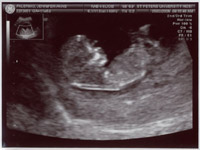

| June 28, 2006 - Twenty Week Ultrasound: IT'S A BOY!!! |

Today was probably the

longest day of my life having to wait for our 3:00pm appointment. I

went to work today, but didn't get much done since I was so excited to

finally find out what we were having. We got to the doctor's and they

took us right away. Within 44 seconds of the technician turning on the

ultrasound machine, she showed us the picture of the legs spread wide open

and it was obvious that we were having a boy!! He was so active

throughout the entire ultrasound, kicking and turning all over the place.

He is absolutely beautiful!!! I am in love with him already. He

weighed 13.5 ounces and he is perfect and healthy!! We are so excited

to start planning the nursery for our little man. Here are the

ultrasound pics from today. Enjoy!! ~Jen

View from the backside |